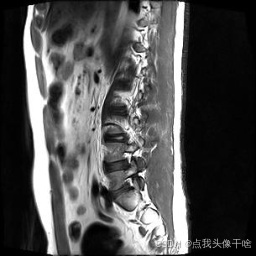

想象一下,你给AI看一张脊椎的核磁共振(MRI)照片,它就能像经验丰富的医生一样,把照片里每一块骨头、每一节椎间盘都给你清清楚楚地标记出来。这个系统干的就是这个酷炫的事儿!

- 原图:就是一张张脊椎的MRI扫描图。